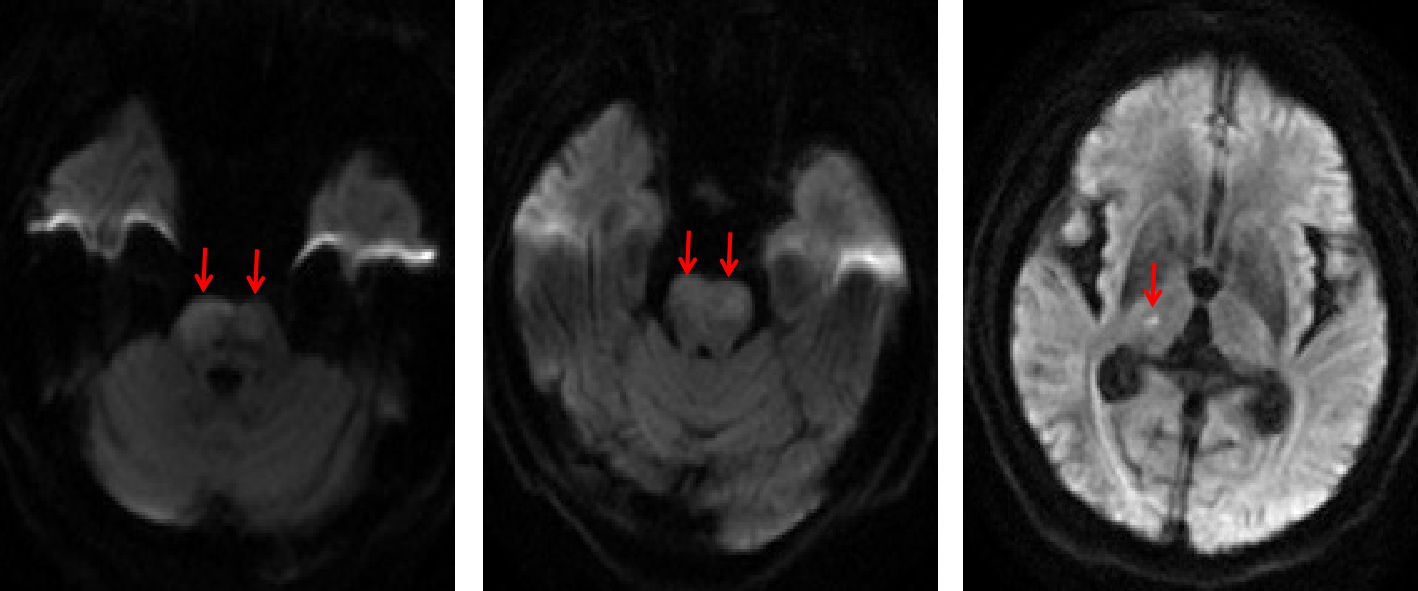

患者洪某,男,68岁,既往长期高血压病史,控制不佳。9小时前晨起时出现头晕伴行走不稳,未重视。5小时前突发意识不清,四肢不能活动,大小便失禁。接诊患者后急诊科、神经内科、影像科及检验科等立即启动脑卒中绿色通道,第一时间完成头颅磁共振,明确诊断急性后循环多发脑梗死,脑桥双侧受累。

图1 头颅磁共振,明确诊断急性后循环多发脑梗死,脑桥双侧受累